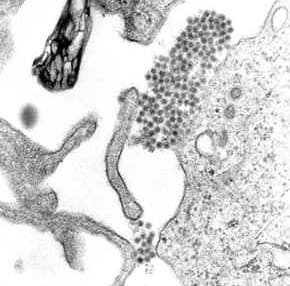

Dengue virus (DENV) is the cause of dengue fever. It is a mosquito-borne, single positive-stranded RNA virus of the family Flaviviridae; genus Flavivirus. Four serotypes of the virus have been found, and a reported fifth has yet to be confirmed, all of which can cause the full spectrum of disease. Nevertheless, scientists' understanding of dengue virus may be simplistic as, rather than distinct antigenic groups, a continuum appears to exist. This same study identified 47 strains of dengue virus. Additionally, coinfection with and lack of rapid tests for Zika virus and chikungunya complicate matters in real-world infections. Dengue virus has increased dramatically within the last 20 years, becoming one of the worst mosquito-borne human pathogens which tropical countries have to deal with. Current estimates indicate that as many as 390 million infections occur each year, and many dengue infections are increasingly understood to be asymptomatic or subclinical. Based on the analysis of the envelope protein, at least three genotypes (1 to 3) are known. In 2013, a fourth serotype was reported. A single report of a fifth serotype DEN-5 in 2015 has not been replicated or further reported on. The rate of nucleotide substitution for this virus has been estimated to be 6.5 per nucleotide per year, a rate similar to other RNA viruses. The American African genotype has been estimated to have evolved between 1907 and 1949. This period includes World War I and World War II, which were associated with considerable movement of populations and environmental disturbance, factors known to promote the evolution of new vector-borne viral species. A Bayesian analysis of all four serotypes estimated that their most recent common ancestor existed about 340 AD (95% confidence interval: 280 BC–850 AD). Until a few hundred years ago, dengue virus was transmitted in sylvatic cycles in Africa, Southeast Asia and South Asia between mosquitoes of the genus Aedes and nonhuman primates, with rare emergences into human populations.